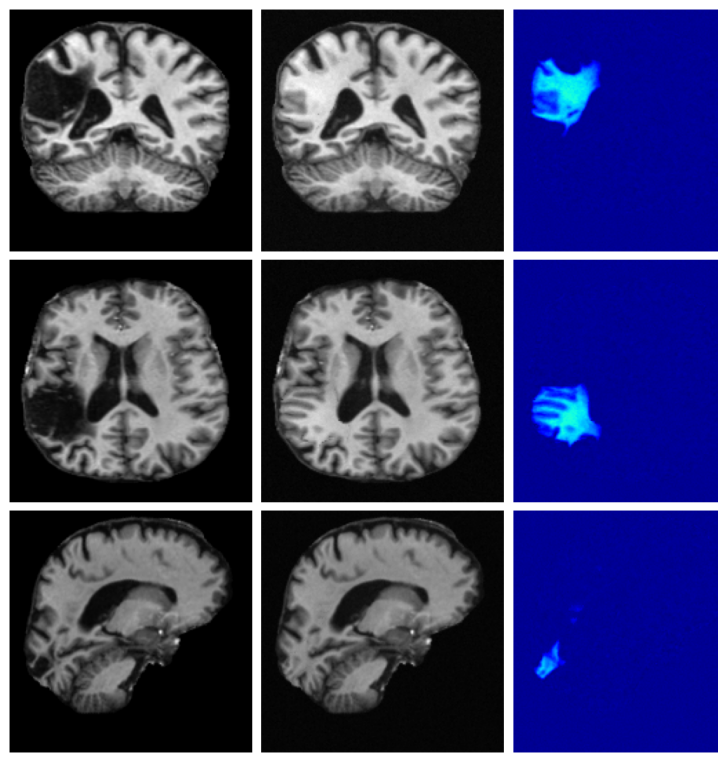

Figure 3 (additional examples in Appendix A.9) shows that SynthSR preserves healthy tissue but struggles with large lesions, while DDPM-2D and DDPM-3D, despite producing high-contrast anomaly maps, generate unrealistic homogeneous inpainting, consistent with their lower performance in Table 3. In contrast, our method yields the most anatomically plausible inpainted regions, although anomaly maps appear subtle due to low contrast between lesions and healthy tissue.

A.9 Additional qualitative inpainting results

Additional qualitative results for the ATLAS and BraTS datasets are given in Figures 12 and 13, respectively.